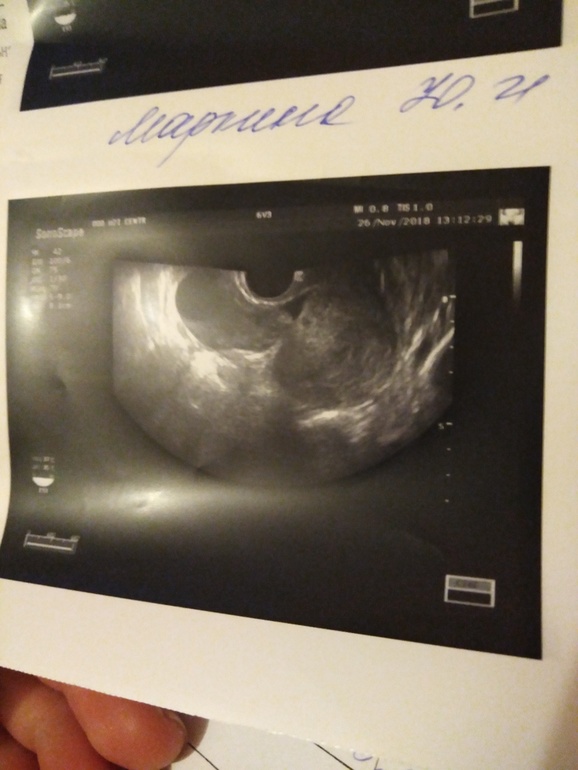

при положительных тестах, сходила на узи, посмотреть эндометрий и была ли овуляция. (я не чувствую себя беременной)

размеры матки:55-44-57

эндометрий 9мм

яичник правый 47-36-48, угол 24мм

левый 27-19-28

желтое тело 18 мм

что на снимке понятия не имею